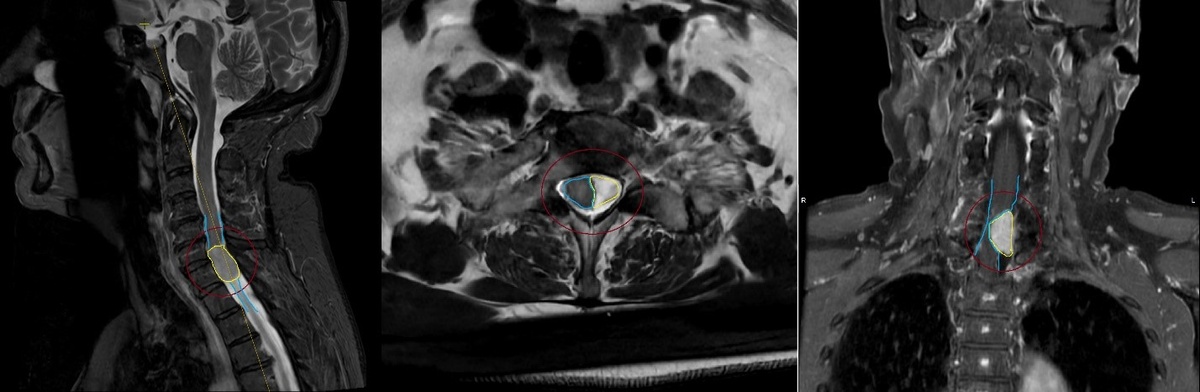

МРТ-исследование шейного отдела позвоночника и спинного мозга с контрастным усилением (до оперативного вмешательства). На уровне С6-С7 позвонков, преимущественно слева, визуализирована опухоль – менингиома (контур выделен жёлтым цветом). Менингиома вызывает грубую компрессию и смещение спинного мозга на данном уровне (максимально до 70-80% позвоночного канала, контур спинного мозга обозначен голубым цветом).

Впоследствии было выявлено, что опухоль является менингиомой, которая располагается на уровне С6-С7 позвонков и вызывает грубую компрессию и смещение спинного мозга на этом уровне. Она относится к доброкачественным опухолям центральной нервной системы (головного и спинного мозга), а точнее — твёрдой мозговой оболочки (ТМО).